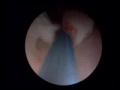

Uterine polyps mayo hospital. Overgrowth of cells in the lining of the uterus (endometrium) ends in the formation of uterine polyps, also known as endometrial polyps. Those polyps are commonly noncancerous (benign), even though a few can be cancerous or can subsequently become cancer (precancerous polyps). Doctoryourself kidney sicknesses. Kidney sicknesses home. Kidney sicknesses kill 60,000 individuals a year and afflict at least eight million more. Dialysis and transplants are steeply-priced, costing taxpayers. Symptoms womb cancer most cancers research uk. Find out about the feasible signs and symptoms of womb cancer and while to see your physician. Bypass to important content. Allow's beat cancer growths (polyps) in the womb lining; Bladder cancer glossary of terms with scientific definitions. Bladder cancer scientific word list includes a list of bladder most cancers related clinical definitions from the medterms clinical dictionary. Uterine polyps ladies's health problem. Uterine polyps are smooth pink outgrowths from the liner of the womb (the endometrium), commonly less than 1 cm in diameter, which frequently flatten to fit the cavity of the. Polyps causes, symptoms & remedies gynaechoice. Polyps can appear at any time of a female's existence and remedy relies upon whether they're on the cervix, uterus or womb. Signs vary, go to now to discover greater.

glossary womenshealth.Gov. A acupuncture a shape of complementary and opportunity medicinal drug that entails inserting skinny needles through the pores and skin at specific factors at the frame to control pain. Uterine polyps cleveland medical institution. Uterine polyps are growths that occur in the endometrium, the internal lining of the uterus. Cleveland sanatorium experts discuss analysis and remedy options. Polyps kinds, treatments, and biopsy healthline. Ladies over forty years of age and women who've had kids are more likely to expand polyps in the uterus. For cervical polyps, records of colon polyps and most cancers; Polyps in uterus signs and symptoms, reasons, removal, treatment. Uterine polyps are commonly asymptomatic, however, while signs appear, these are similar to the signs and symptoms of endometrial most cancers, a more severe circumstance. Liver most cancers integrative remedy program ctca. Integrative liver most cancers treatment. Ctca uses superior technology and integrative oncology offerings that will help you better tolerate remedy and manipulate side consequences. Treatment of uterine polyps management ,. Remedy and control of endometrial polyps d&c, uterine polypectomy surgical operation, medicines, alternative cures. So scared i would have most cancers, ultrasound confirmed. · so scared i might have most cancers, ultrasound confirmed thickening of the liner of the womb, published 31 july 2014 at 1642.

Dizziness and giddiness medical disability hints. Mdguidelines is the most trusted source of incapacity hints, disability periods, and return to paintings facts on dizziness and giddiness. Benign uterine growths signs and symptoms, treatments & causes. Benign uterine growths signs and treatments. Study adenomyosis, uterine fibroids, and uterine polyps. Examine about uterine growths after menopause. Endometrial polyps obgyn. As our ability to look within the uterus improves, many ladies are informed they have got a commonplace abnormality of the uterine lining, known as endometrial polyps. An. Malignant uterine polyps analysis, treatment &. Malignant uterine polyps can spread and recur, and the most not unusual cause is the presence of polyps or tumors within the uterus. Despite the fact that most cancers is uncommon, Polyps in uterus diseaseszoom. Uterine polyps are normally asymptomatic, however, whilst signs and symptoms seem, those are similar to the symptoms of endometrial most cancers, a extra critical circumstance. What's the ordinary liver measurement? Hepatitis c medhelp. · i simply have a curiousity question. I've been wondering if there's a normal liver dimension price. As an instance like normal parameters among 12.0 15.